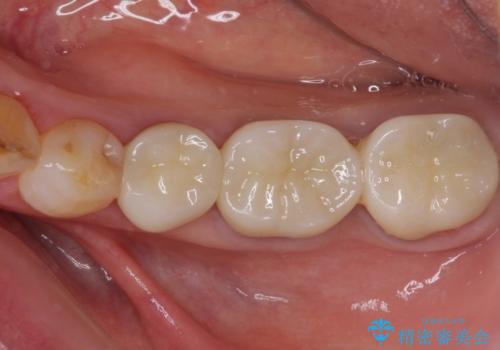

全ての奥歯の銀歯をセラミックに メタルフリー治療

土台に含まれている金属も含め、奥歯の金属は全て除去し、オールセラミッククラウンやセラミックインレーにて治療することとしました。

途中体調を崩されてしまい、その間に仮歯が外れてしまうなど、治療期間が長引いてしまいました。

治療期間はかかってしまいましたが、念願のメタルフリーとなり、患者様には大変満足していただきました。